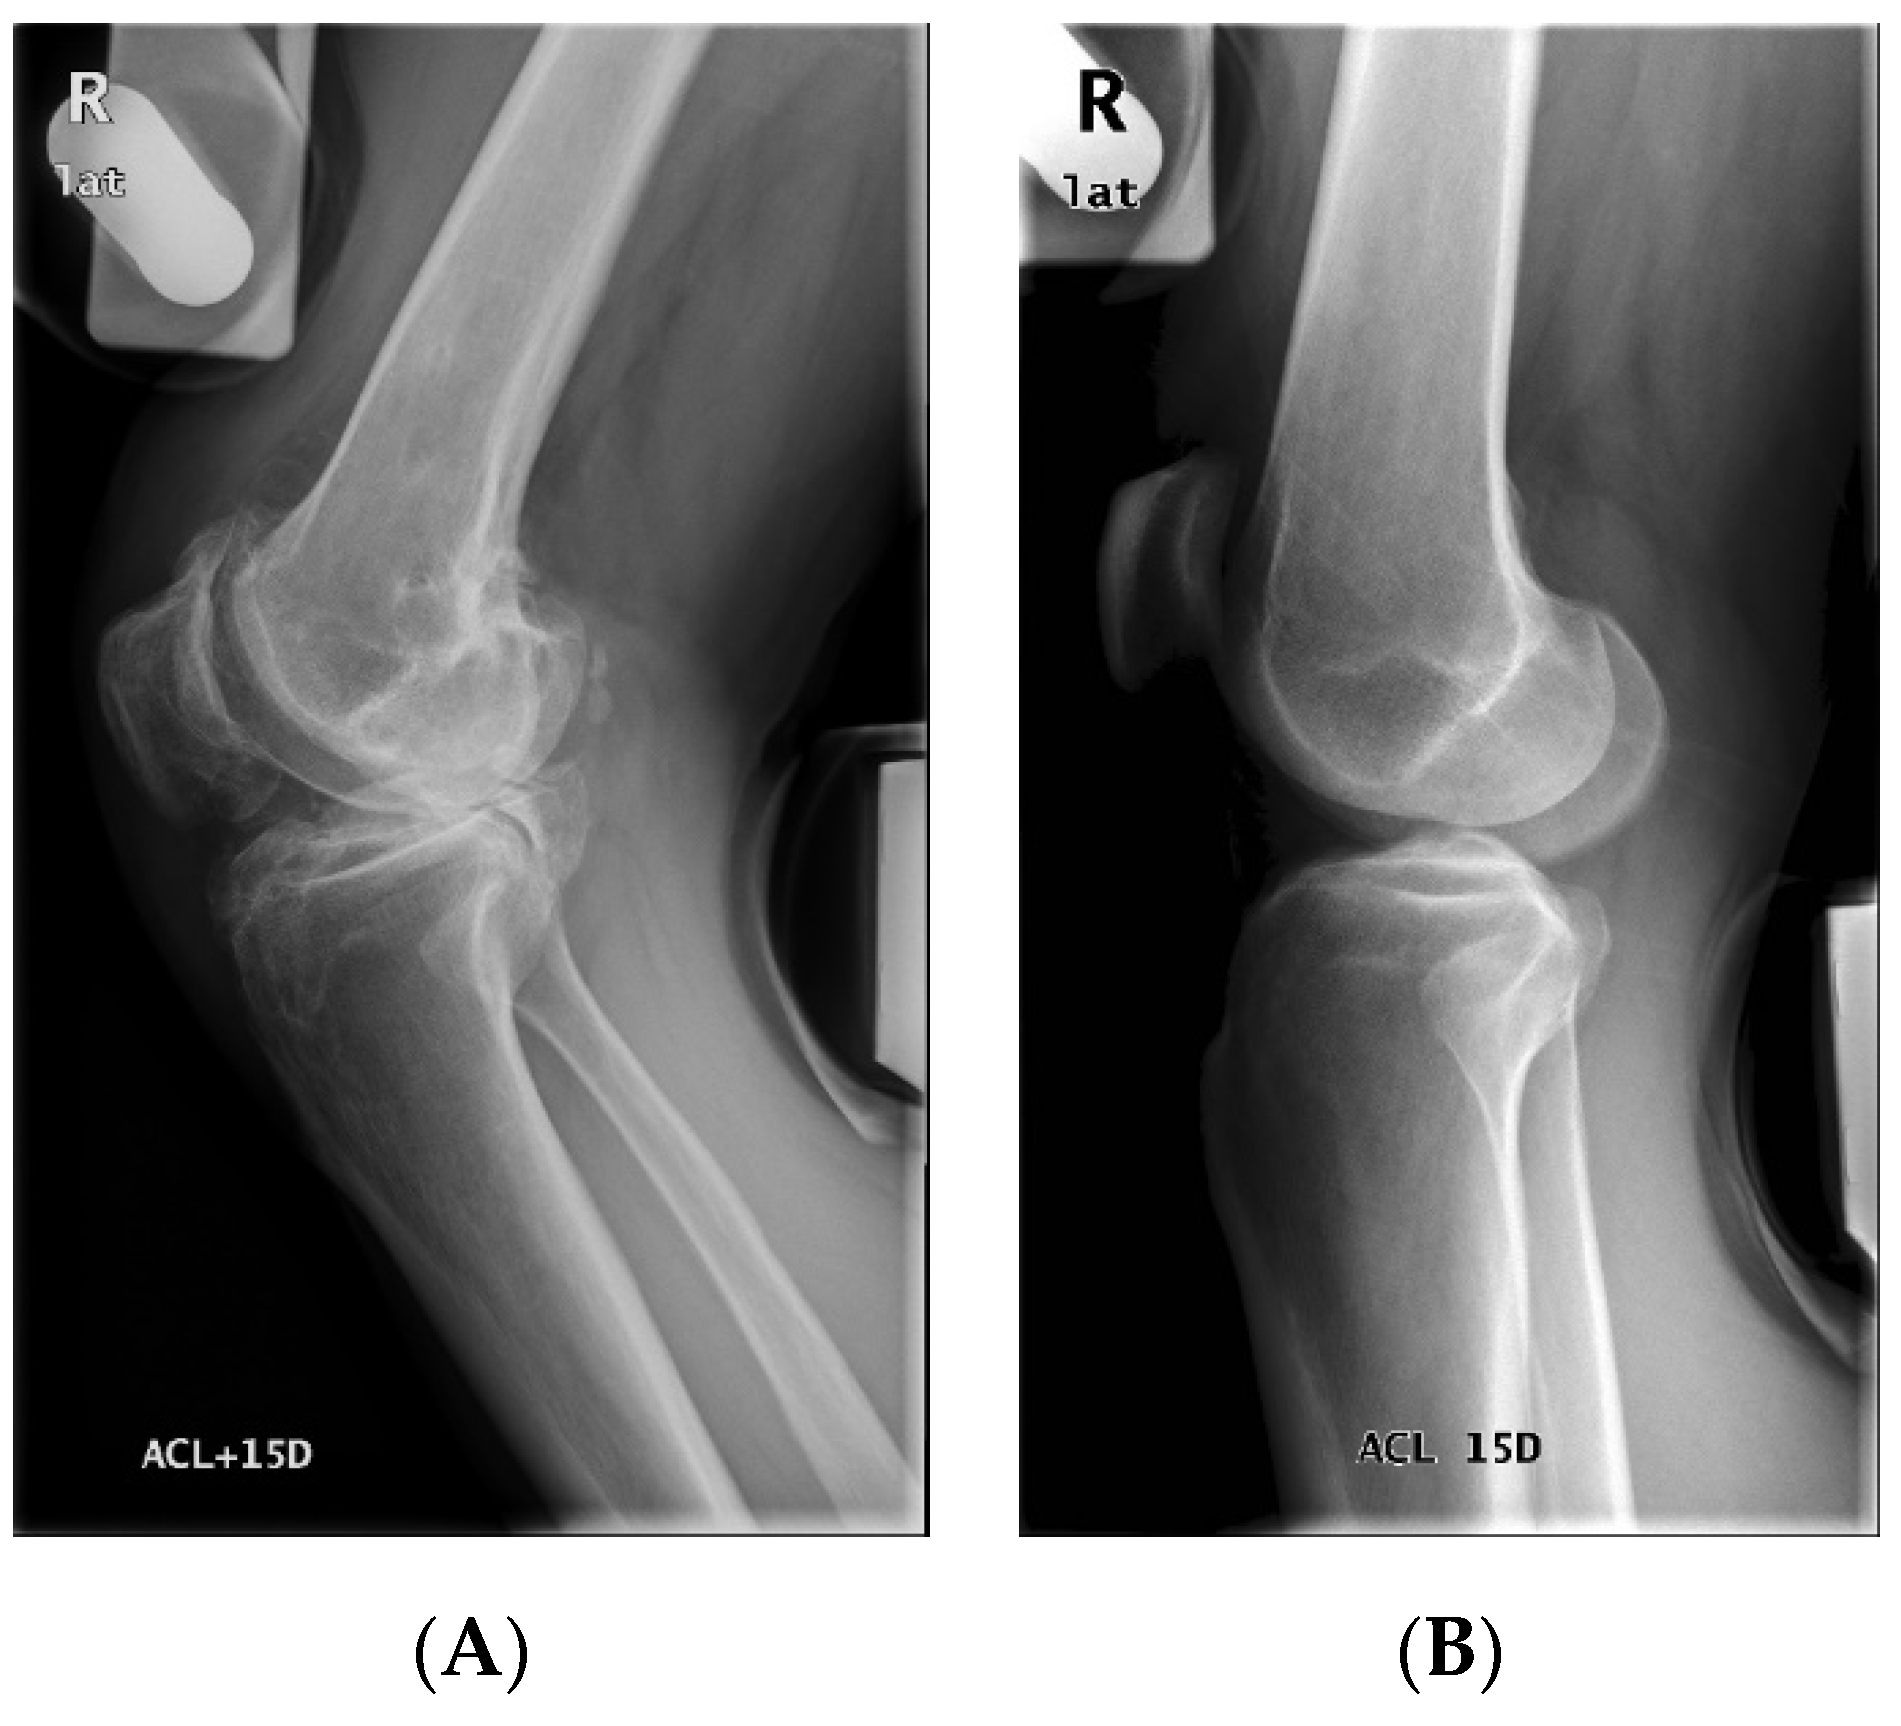

Figure 3.

The segmentation results of stress radiography for anterior cruciate ligament (ACL) injury. In this case, the lateral (lat) projection views of the right (R) knee before and after exerting a force of 15 daN (+15D) posteriorly on the tibia by a stress device were taken. The anterior edge and the posterior edge of both femur and tibia were segmented (cyan and orange dots) and used to calculate the femoral axis and the tibial axis (cyan and orange straight lines). The condyle contours (white and yellow curves) were also segmented.